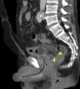

Air hose injury of rectum